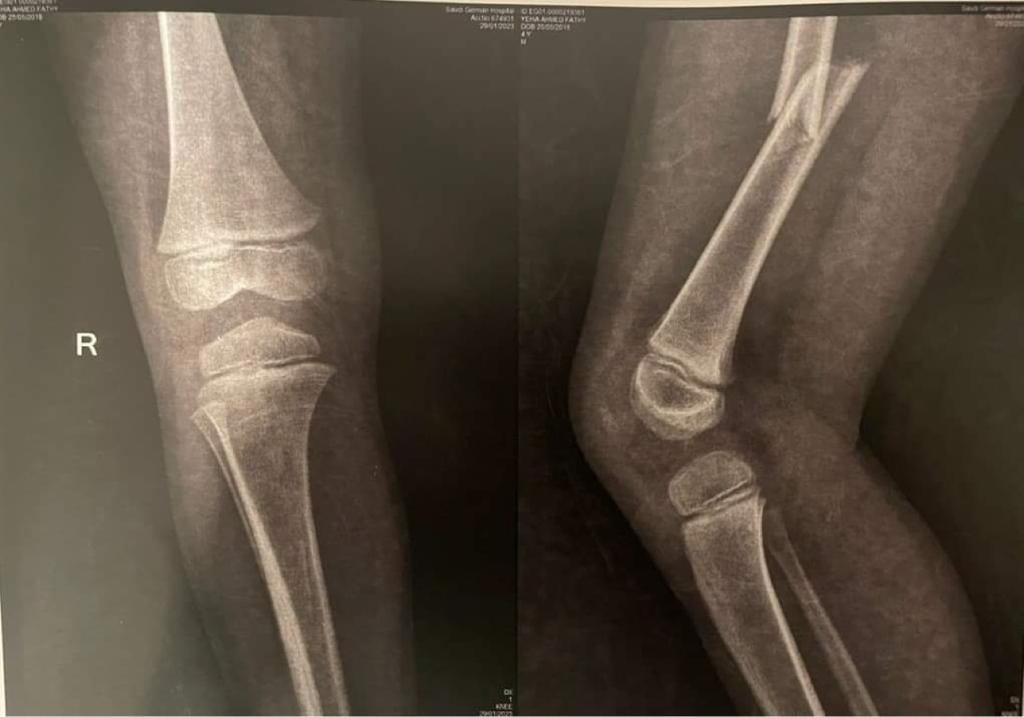

وقال والد الطفل أحمد فتحي لـ القاهرة 24: أصيب الطفل في كسر في الفخذ، وأجريت له عملية تركيب مسامير، وسيبدأ الطفل في رحلة العلاج الطبيعي، وبعد 4 شهور سيتم إجراء عملية أخرى له.

وأخبرت المستشفى والدة الطفل أنه مصاب بكسر في عظمة الفخذ، ويحتاج إلى عملية جراحية، ومن بعدها علاج طبيعي ويحتاج إلى عملية أخرى.